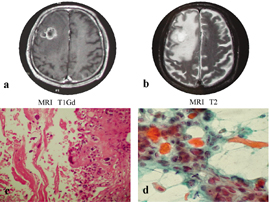

Case 3. Malignant Lymphoma(primaryj.(ŽÊ^‚Rj

‰æ‘œ‚ðŒ©‚Ä‚Ý‚æ‚€

d–Œ‚ɐڂ·‚邿‚€‚ɉE‘å”]‚ÉMRI T1Gd‚Åenhance‚³‚ê‚émass‚ð”F‚ß‚éD“à•”‚Í‚â‚â•s‹Ïˆê‚ŁC‚»‚ÌŽüˆÍ‚É•‚Žî«•ω»‚ð”F‚ß‚é(ajD”]ŽÀŽ¿ŠO‚©C”]ŽÀŽ¿“à‚©”»’f‚̓‚¢‘œ‚Å‚ ‚éD

”wŒi‚ɂ͕ϐ«‚µ‚œ—±ó•š‚ð”F‚ß‚éDN/C”ä‘åCŠjƒNƒƒ}ƒ`ƒ“‚Ì‘‰Á‚ÆŠjŒ^•s®‚𔺂€‰~Œ`×–E‚ªŒ©‚ç‚ê‚é(cjDGiemsaõF‚ł͍זEŽ¿‚ª–Ÿ—ĂɊώ@‚³‚ê‚é(d)DMalignant Lymphoma‚̍זE‘œ‚Å‚ ‚éD

ŒŒŠÇŽüˆÍ‚ÉŽîᇍזE‚ªW‘°‚µ‚Ä‚¢‚éDMalignant Lymphoma‚Ì‘gD‘œ‚Å‚ ‚éD

‡@”]ŒŽ”­malignant lymphoma‚Ídiffuse large cell type‚ª‘œ‚­Cp’†v‘¬f’f‚ł͍זEf’f‚ªˆÐ—͂𔭊ö‚Å‚«‚éŽîᇂł ‚éD‡Ap‘O‚Ì•úŽËü—Ö@‚âƒXƒeƒƒCƒh“Š—^‚É‚æ‚èŽîᇍזE‚ÌŒž­CŒ`‘ԕω»CŽüˆÍgliosis‚Ȃǂ̕ω»‚ð‹N‚±‚·‚œ‚߁Cv‘¬f’f‘O‚Ƀ`ƒFƒbƒN‚·‚é•K—v‚ª‚ ‚éD‡BŒŒŠÇŽüˆÍ(Virchow-Robino)‚ɐZ‚µ‚Ăт܂ñ«‚É‘B‚·‚éD‘gD•W–{‚ł͌ŒŠÇŽüˆÍ‚ÉŽîᇍזE‚ªW‘°‚·‚鑜‚ª“Á’¥“I‚Å‚ ‚éDMRI T1Gd‚ł͔]ŽÀŽ¿‚Æenhance•”ˆÊ‚Ì‹«ŠE•”‚©‚çÌŽæ‚³‚ꂜ‘gD‚ÉŒ©‚ç‚ê‚鎖‚ª‘œ‚¢D‡Cy‘fR‘Ì–@‚É‚æ‚éf’f‚Í‘Œ‚Ì‘ŸŠí‚Æ“¯—l‚Å‚ ‚éD

ŽÊ^‚R Case 3.

Malignant@Lymphoma.

ò_ MRI T1 Gd@ ò` HE x100.

òa Pap x400@@òb Giemsa x 400